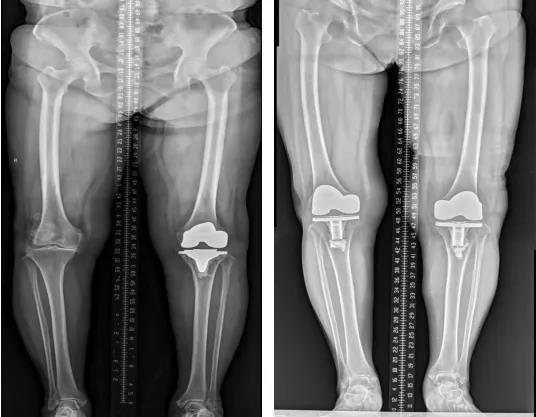

(三)膝骨关节炎全膝关节置换术

膝关节外科技术力量雄厚,科室配备医护人员30人,其中,主任医师5名,副主任医师3名,主治医师3名,住院医师4名,博士1名,硕士研究生4名。开放床位48张。该科擅长对膝关节严重创伤(包括股骨远端骨折、髌骨骨折、胫骨平台骨折等)、膝骨关节炎阶梯化治疗、保膝治疗、膝关节微创单髁置换术、全膝关节置换术、膝关节翻修术具有丰富的临床诊疗经验,追求微创、无痛、快速康复。对膝关节骨性关节炎采取阶梯化治疗方案,坚持中西并重、内外兼治的原则,取得满意的治疗效果。早期利用中医中药的传统优势,使用中医外治法,例如烫熨治疗、中药涂擦、雷火灸、中药塌渍等,同时辩证内服本院中药制剂及内服方药以及配合西药治疗,开展健康教育,运用运动疗法、物理治疗等辅助支持;中期开展软骨修复、截骨术、单髁置换术、髌股关节置换术等;对于终末期的膝关节OA采用全膝关节置换术。【膝关节外科主要特长】 (一)膝骨关节炎高位截骨术